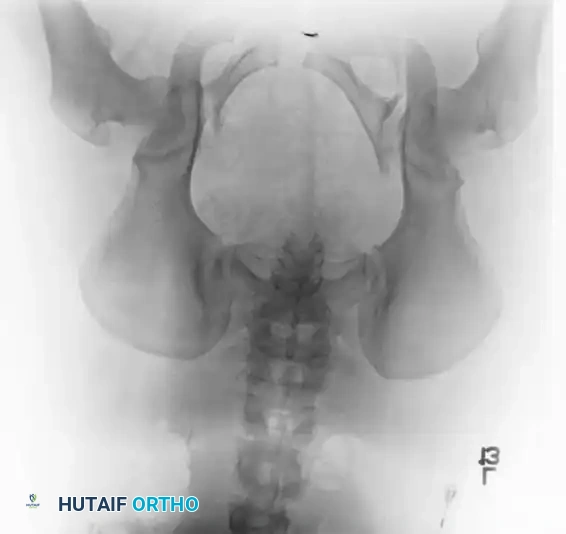

Radiographic Evaluation

Standard evaluation begins with an Anteroposterior (AP) pelvis radiograph. However, definitive surgical planning requires specialized views and advanced imaging.

• Inlet View: Directed 45 degrees caudad. Best evaluates anterior-posterior translation, internal/external rotation, and sacral impaction.

• Outlet View: Directed 45 degrees cephalad. Best evaluates vertical translation and sacral foraminal anatomy.

• CT Scan: The gold standard for evaluating posterior ring injuries, sacral dysmorphism, and preoperative planning for percutaneous fixation.